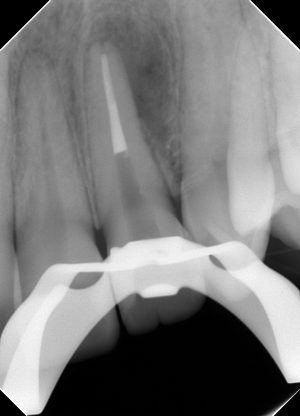

3カ月。

治癒傾向はありますが、まだまだ大きいですね。